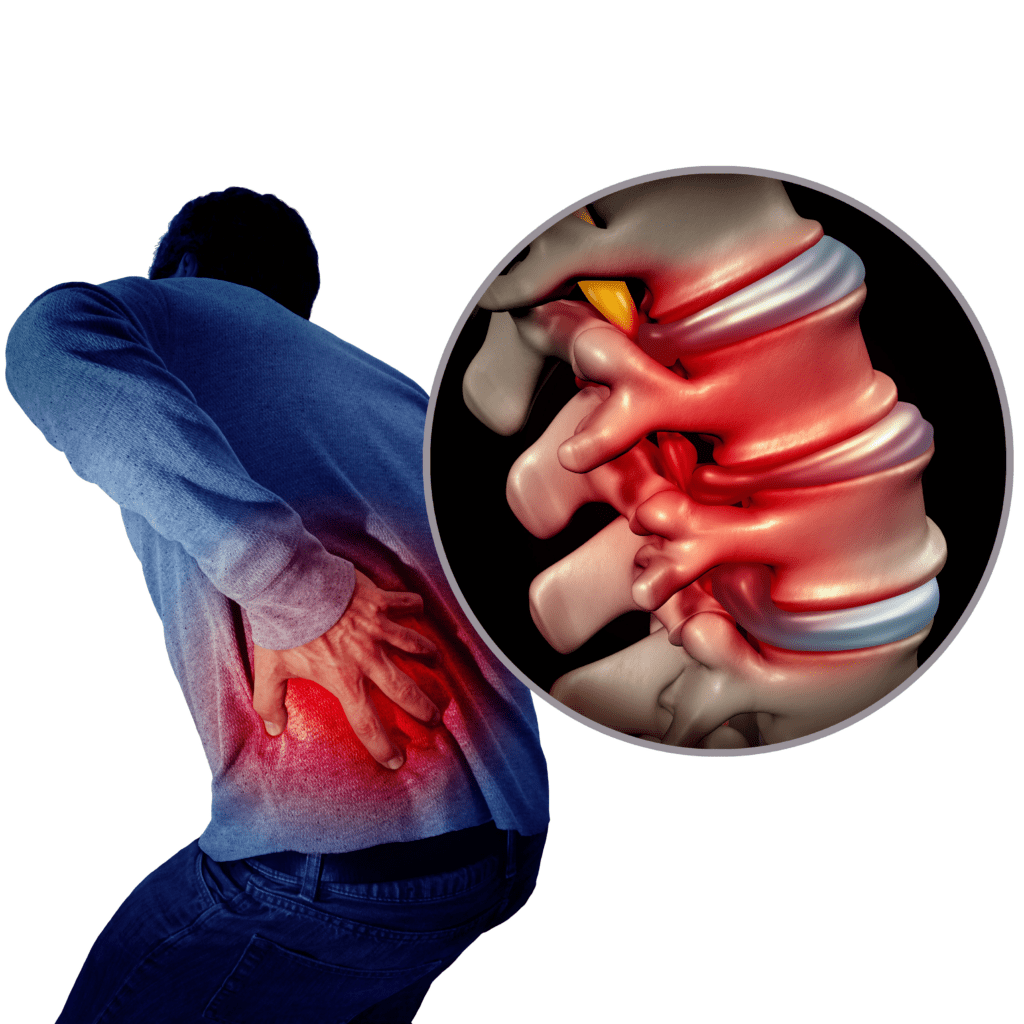

pictures of bulging discs in lower back

Bulging disc-Lower back pain

Sciatica, Spinal Stenosis, Bulging Disc & Other Disc Conditions